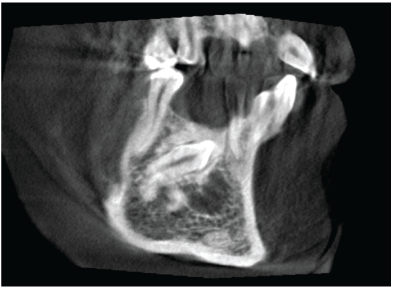

Figure 3: CBCT, sagital view showing impacted mandibular right canine and a unilocular cyst seen below its crown.

There is well defined unilocular radiolucency in the lower anterior area below the crown of impacted tooth #43. This could be OKC or simple bone cyst (Figure 3).